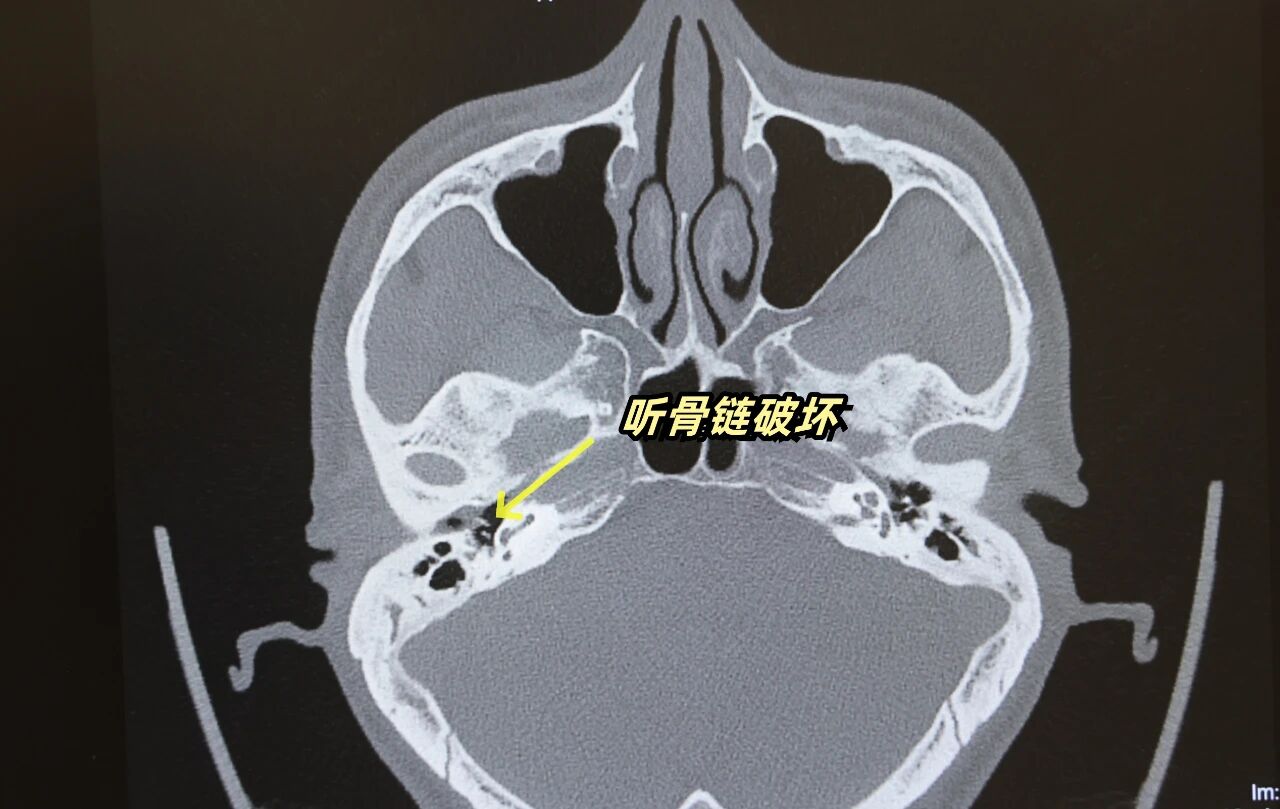

乳突CT检查提示:右侧上鼓室中耳胆脂瘤,听骨链有破坏,并伴有双侧中耳乳突炎。